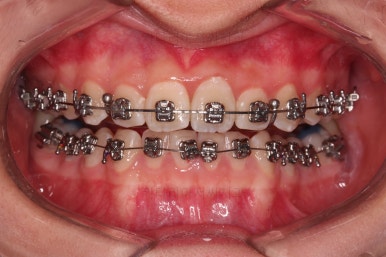

1. 초진

초진 시 입안의 모습입니다.

눈에 띄는 부분은 당연히 앞니가 삐뚤고, 앞니 하나가 앞으로 튀어나온 모습인데요.

자세히 관찰해 보면 다른 문제점들이 보입니다.

우선 위아래 앞니가 깊숙히 맞물려 있는 과개교합 양상인데요.

깊게 맞물려 있으면 기능적으로도 좋지 못하고 입술의 볼륨감에도 부정적이며 치아도 많이 마모가 되기 쉽습니다.